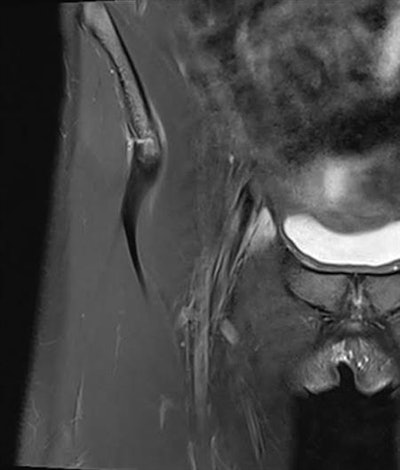

I have worked a lot with hip, knee, and ankle imaging, especially MRI. Injury to the cruciate ligaments, posteromedial and posterolateral corner of the knee has been a special interest, as well as injuries around the ankle. However, the spectrum of sports injuries covers all joints, both upper and lower limb, and every day there is a new challenge and something new to learn.

Imaging can detect both subtle and obvious injuries associated with sporting activity. Early stress reactions in bone, tendons, and soft tissues can be seen, as well as all sorts of ruptures and fractures. However, some injuries are subtle, and if you don't look for them, you will not find them. A sports radiologist must look for smaller changes than other radiologists are used to. This may be because the athlete is imaged very early after an injury or after the start of a complaint, and smaller injuries may be more important in an athlete than in other patients.